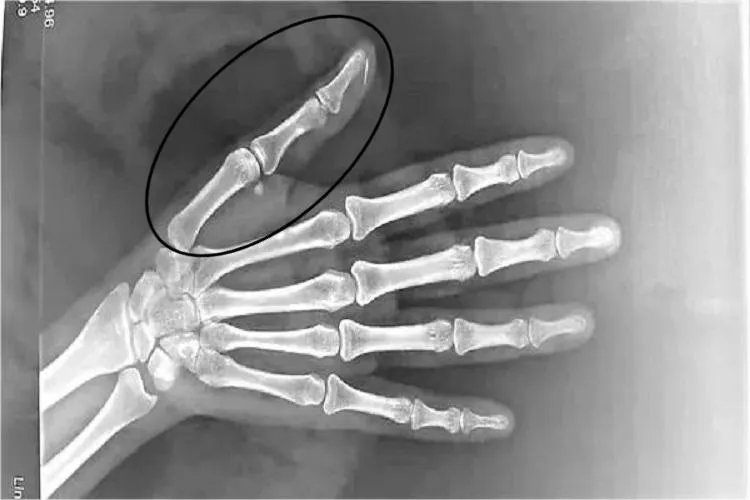

的有关信息介绍如下:概述大拇指的骨头称为指骨,大拇指仅有两节指骨,分别为近端指骨和远端指骨。大拇指的近端指骨、远端指骨及指间关节使其具备了正常的生理功能,能够完成屈伸运动。结构手部有14个指骨,每个指骨都可分为近节指骨、中节指骨、远节指骨,大拇指只有近节指骨和远节指骨。指骨也是小型长骨,指骨的近侧端为底,中部为体,远侧端为滑车。指间关节由各指相邻两节指骨的底和滑车构成,拇指仅有两节指骨,所以只有一个指间关节。